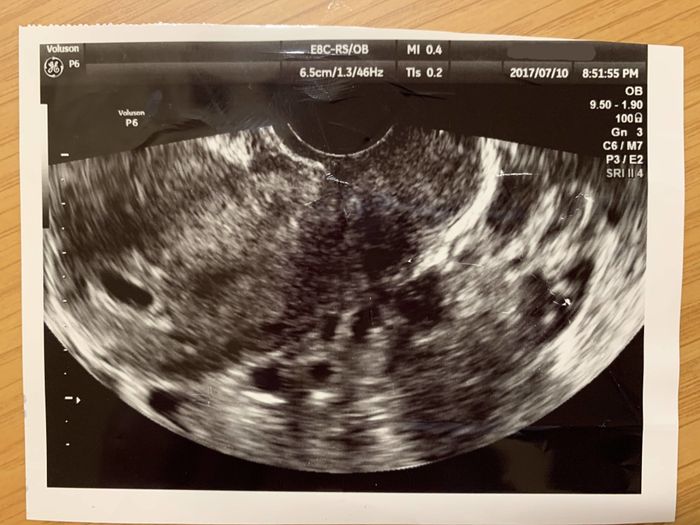

妊娠5週目 おなかの中にやってきた3人目の赤ちゃん!

上の子を二人とも不妊治療によって授かったこともあり、まさか自然に妊娠するとは思ってもいませんでした。体調不良も「夏カゼでもひいたかな?」と思っていたのですが、もしかしたらと思い妊娠検査薬で検査をしたところ、まさかの陽性! その時は、喜びよりも「なぜ?」とびっくりする気持ちの方がが強かったのを覚えています。病院のエコー検査で、ちゃんと胎嚢が確認できたとき、「ようこそ、ママのおなかへ!」と湧き上がる喜びでいっぱいでした。